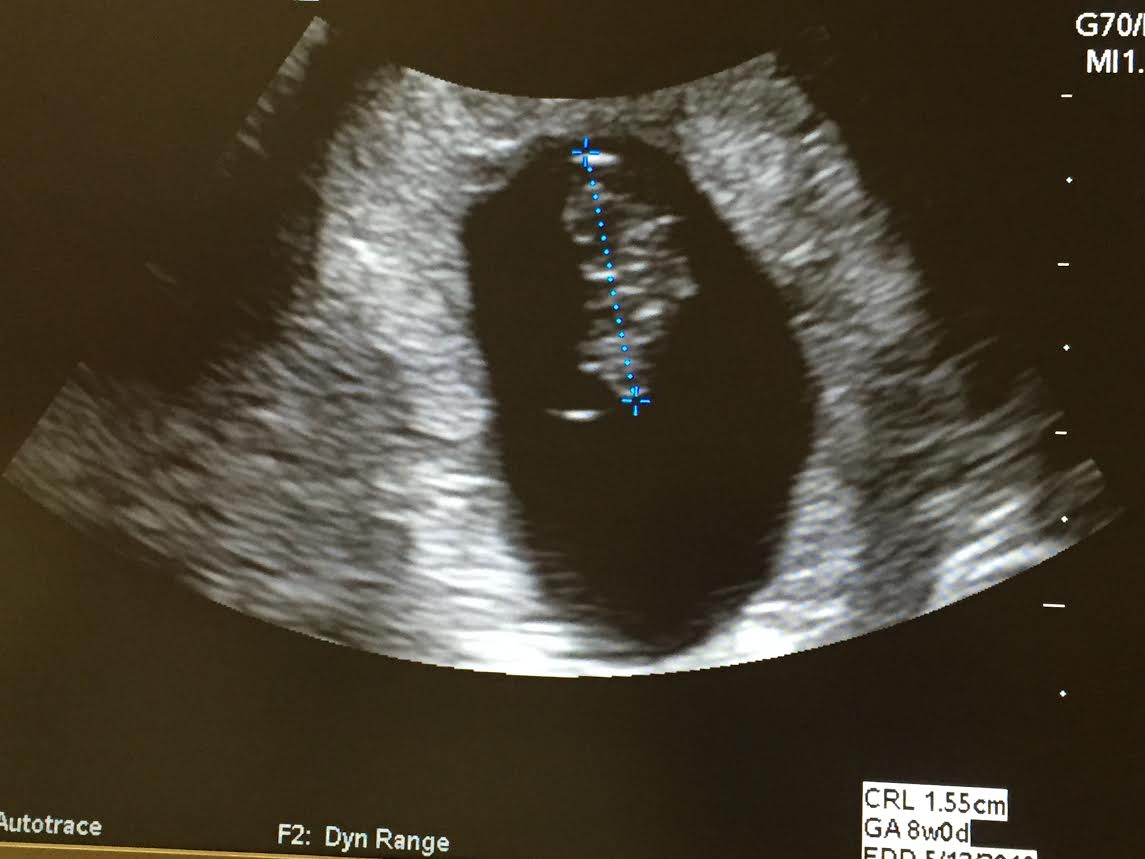

A little blurrier than others, but I am at 8w by lmp and Speck measured as 8w4d and heartbeat at 150! Such a relief given past experiences! We aren't out of the woods until 1st trimester ends of course, but so thrilled there is a baby in there, and all is well at this point!